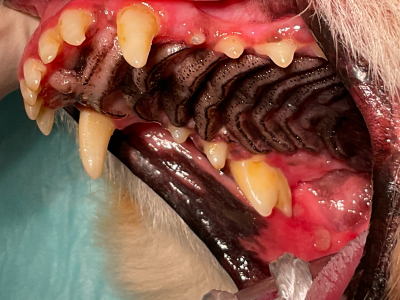

術前

のどまで真っ赤に腫れ上がっていて、これでは食事はつらいことでしょう。